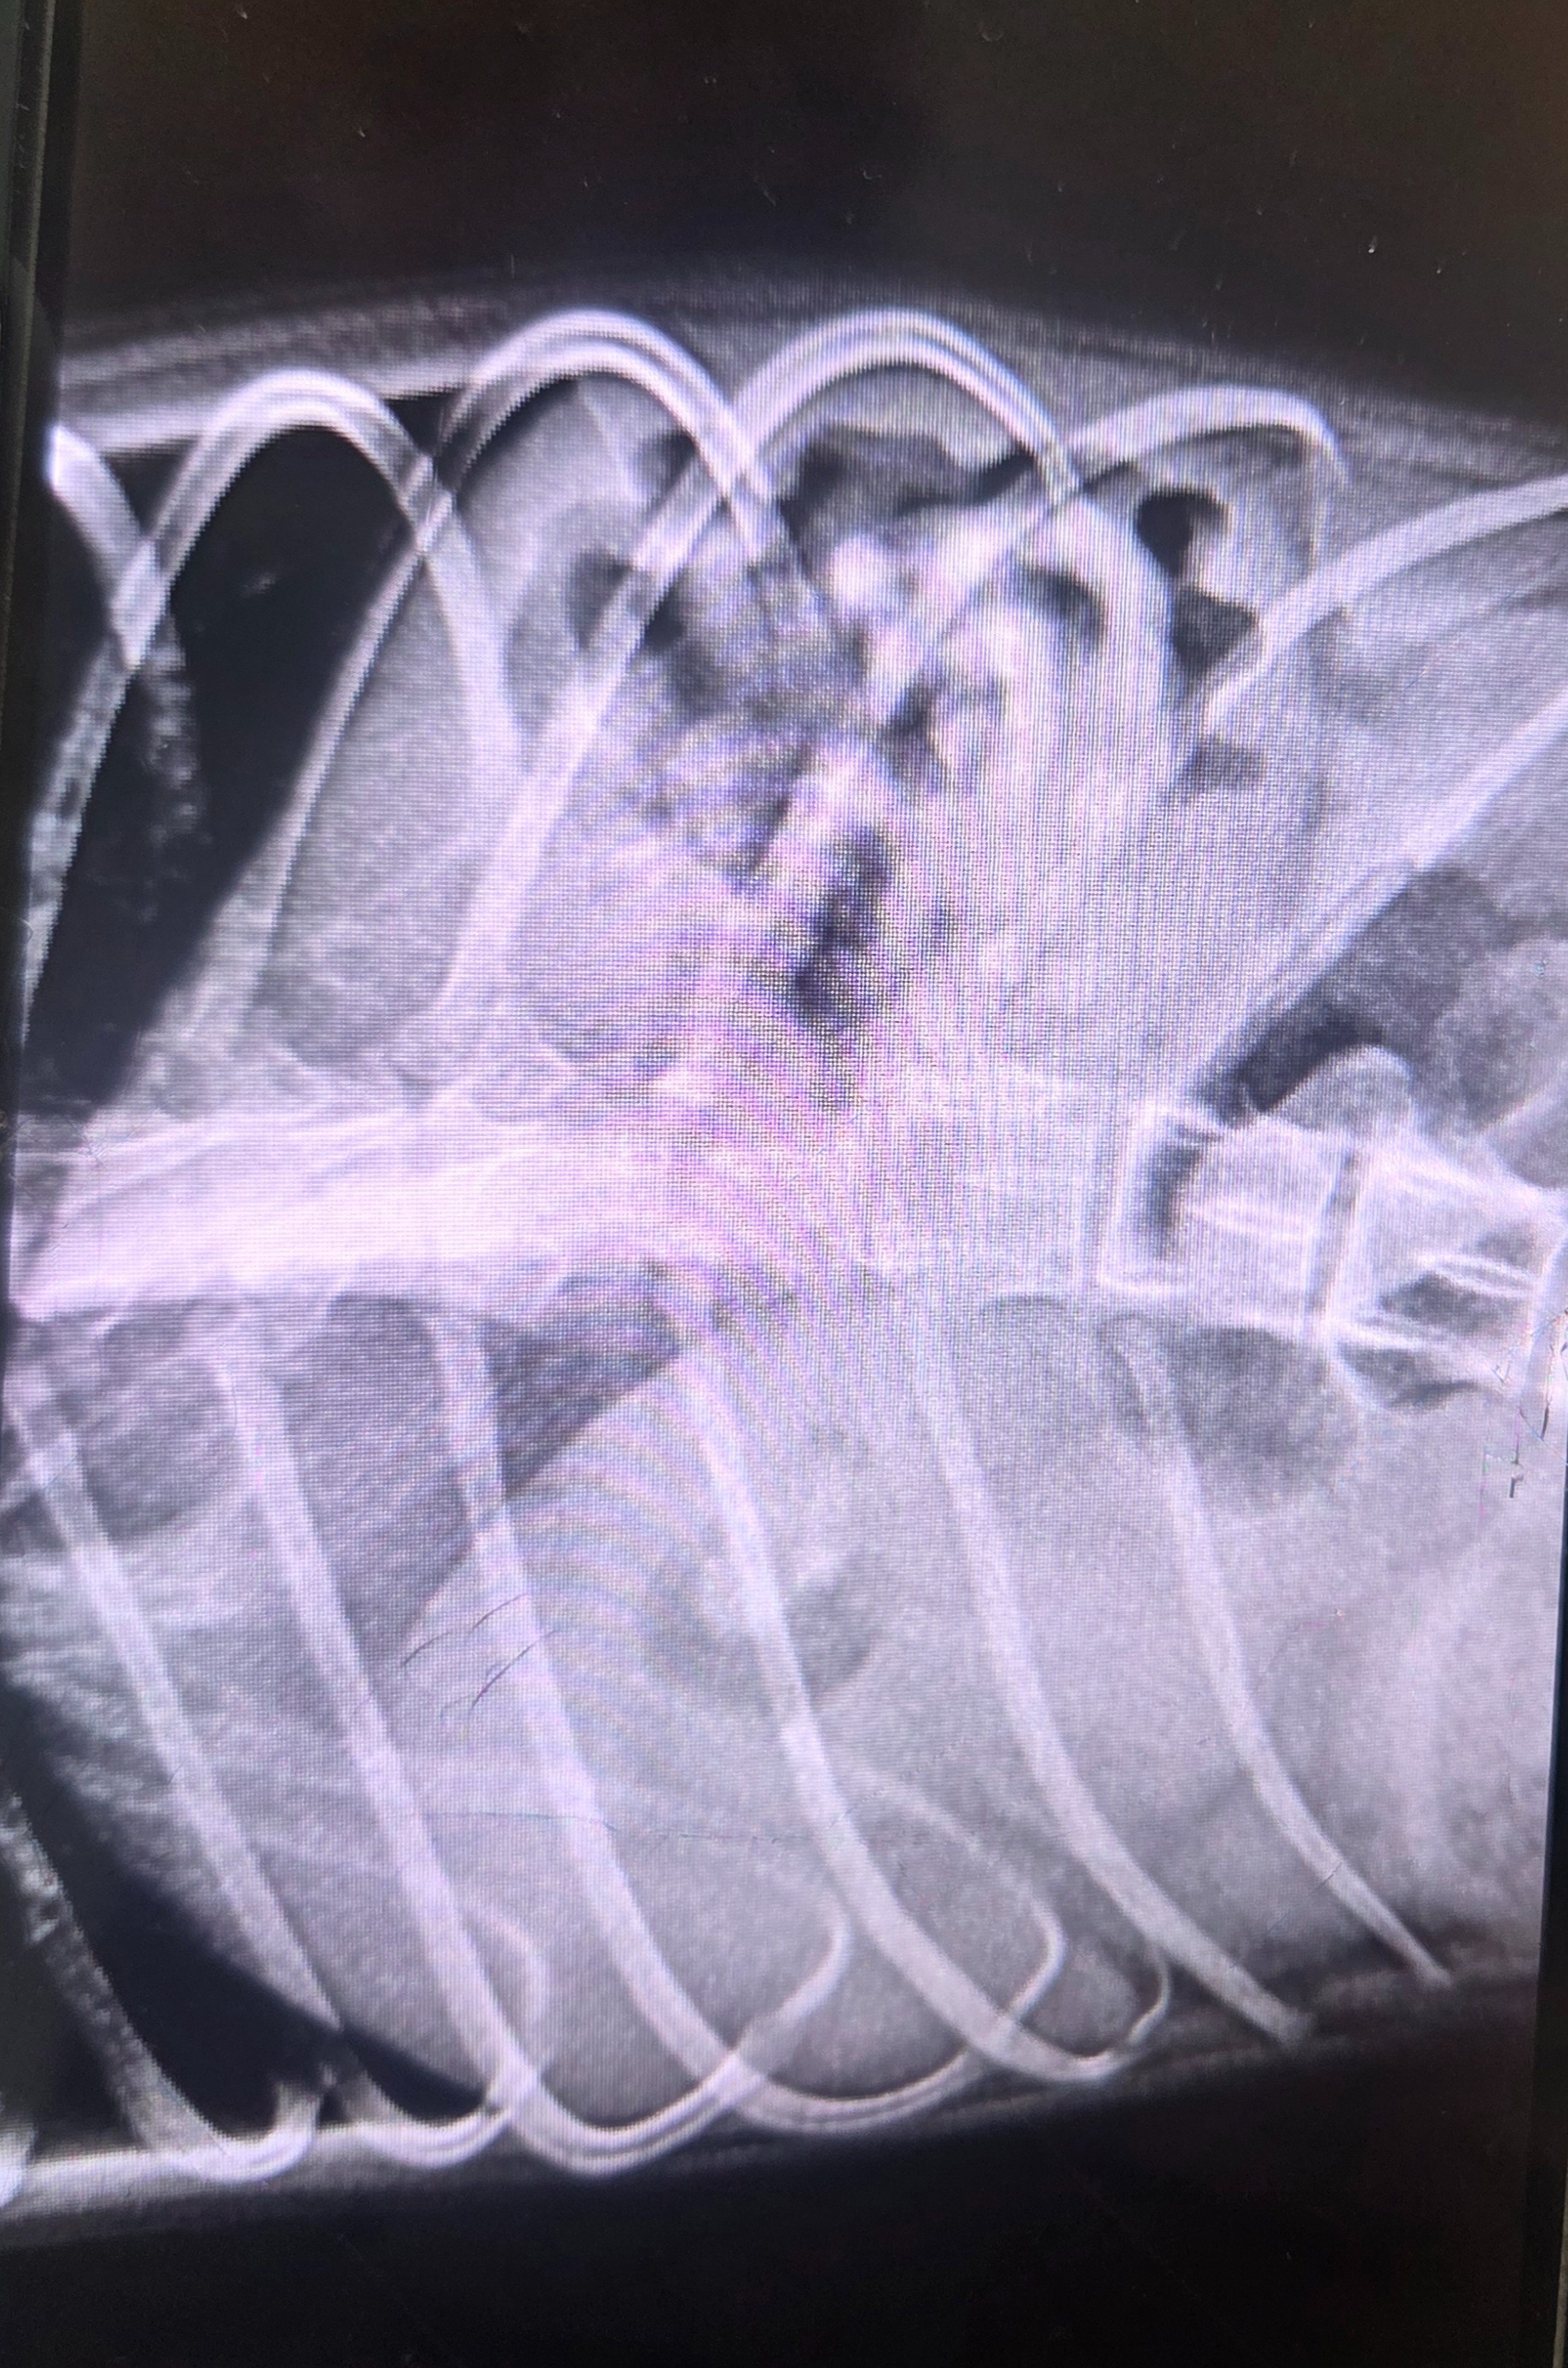

Moon swallowed a foreign object that caused a dangerous blockage in his stomach. The veterinarian confirmed this is life-threatening, and that emergency surgery is the only way to save his life.